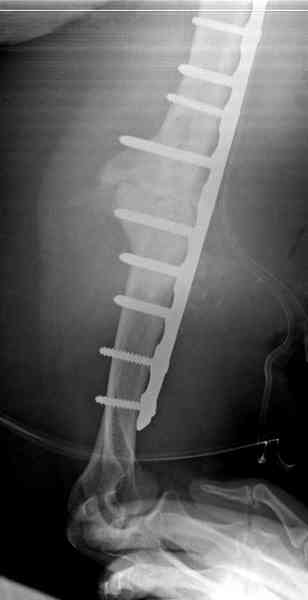

Хотя сам не стороннник применения более массивных

имплантов для плеча, но для этого случая сделали

исключение. На снимке 4А диаметр мягких ткани около 20 см, при весе больной более 135 кг, и также выступление Андрея Волны подстегнуло к применению более массивной 4.5 мм локинг пластины.

Биологические стимуляторы типа Synthes chronOS мы

применяем только для закрытия дефекта в закрытом

пространстве, например в тибиал плато, пилоне и

ацетабулярных переломах.

Несмотря на то, что компания рекомендует, что препарат является остеоиндуктивным, но мы считаем, что препарат надо применять для заполнения дефектов, потому что "indicated for use in bony voids or gaps that are not intrinsic to the stability of the bony structure.

chronOS is indicated for use treatment of bony defects created surgically or through traumatic injury".

А для стимулирования мы применили массу из состава:

OP1 с деминерализованной костью, добавив к ним еще

красную часть, приготовленную из крови больной.

Взятая перед операцией кровь в количестве 80 мл

провели через центрифугу и без сывороточной части

красную матрицу добавили к остальным.

С такой массой наверное ложный сустав "over killed", но надеюсь, что-то из них при такой фиксации окажет стимулирующее действие.